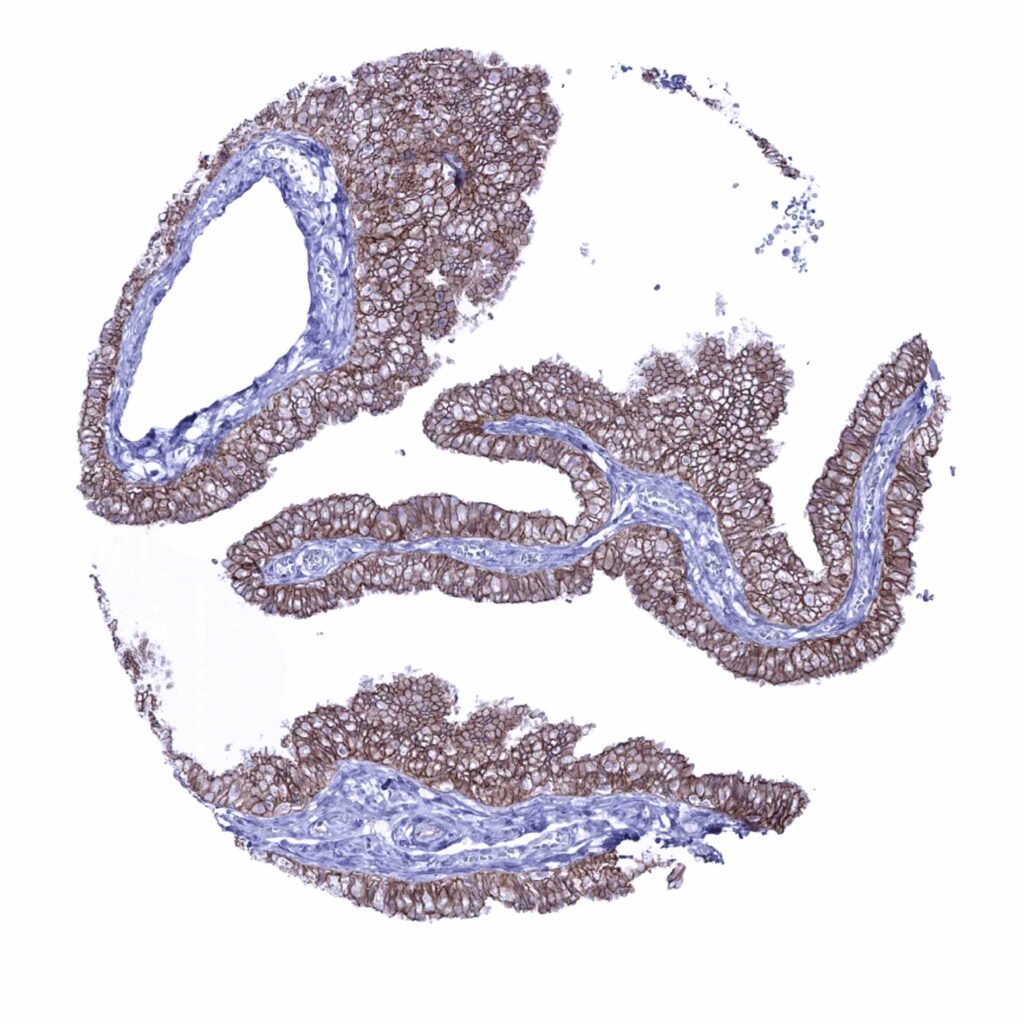

Fallopian tube, mucosa – Membranous occludin positivity is diffuse but strongest at the apical membrane (occludin immunohistochemistry)